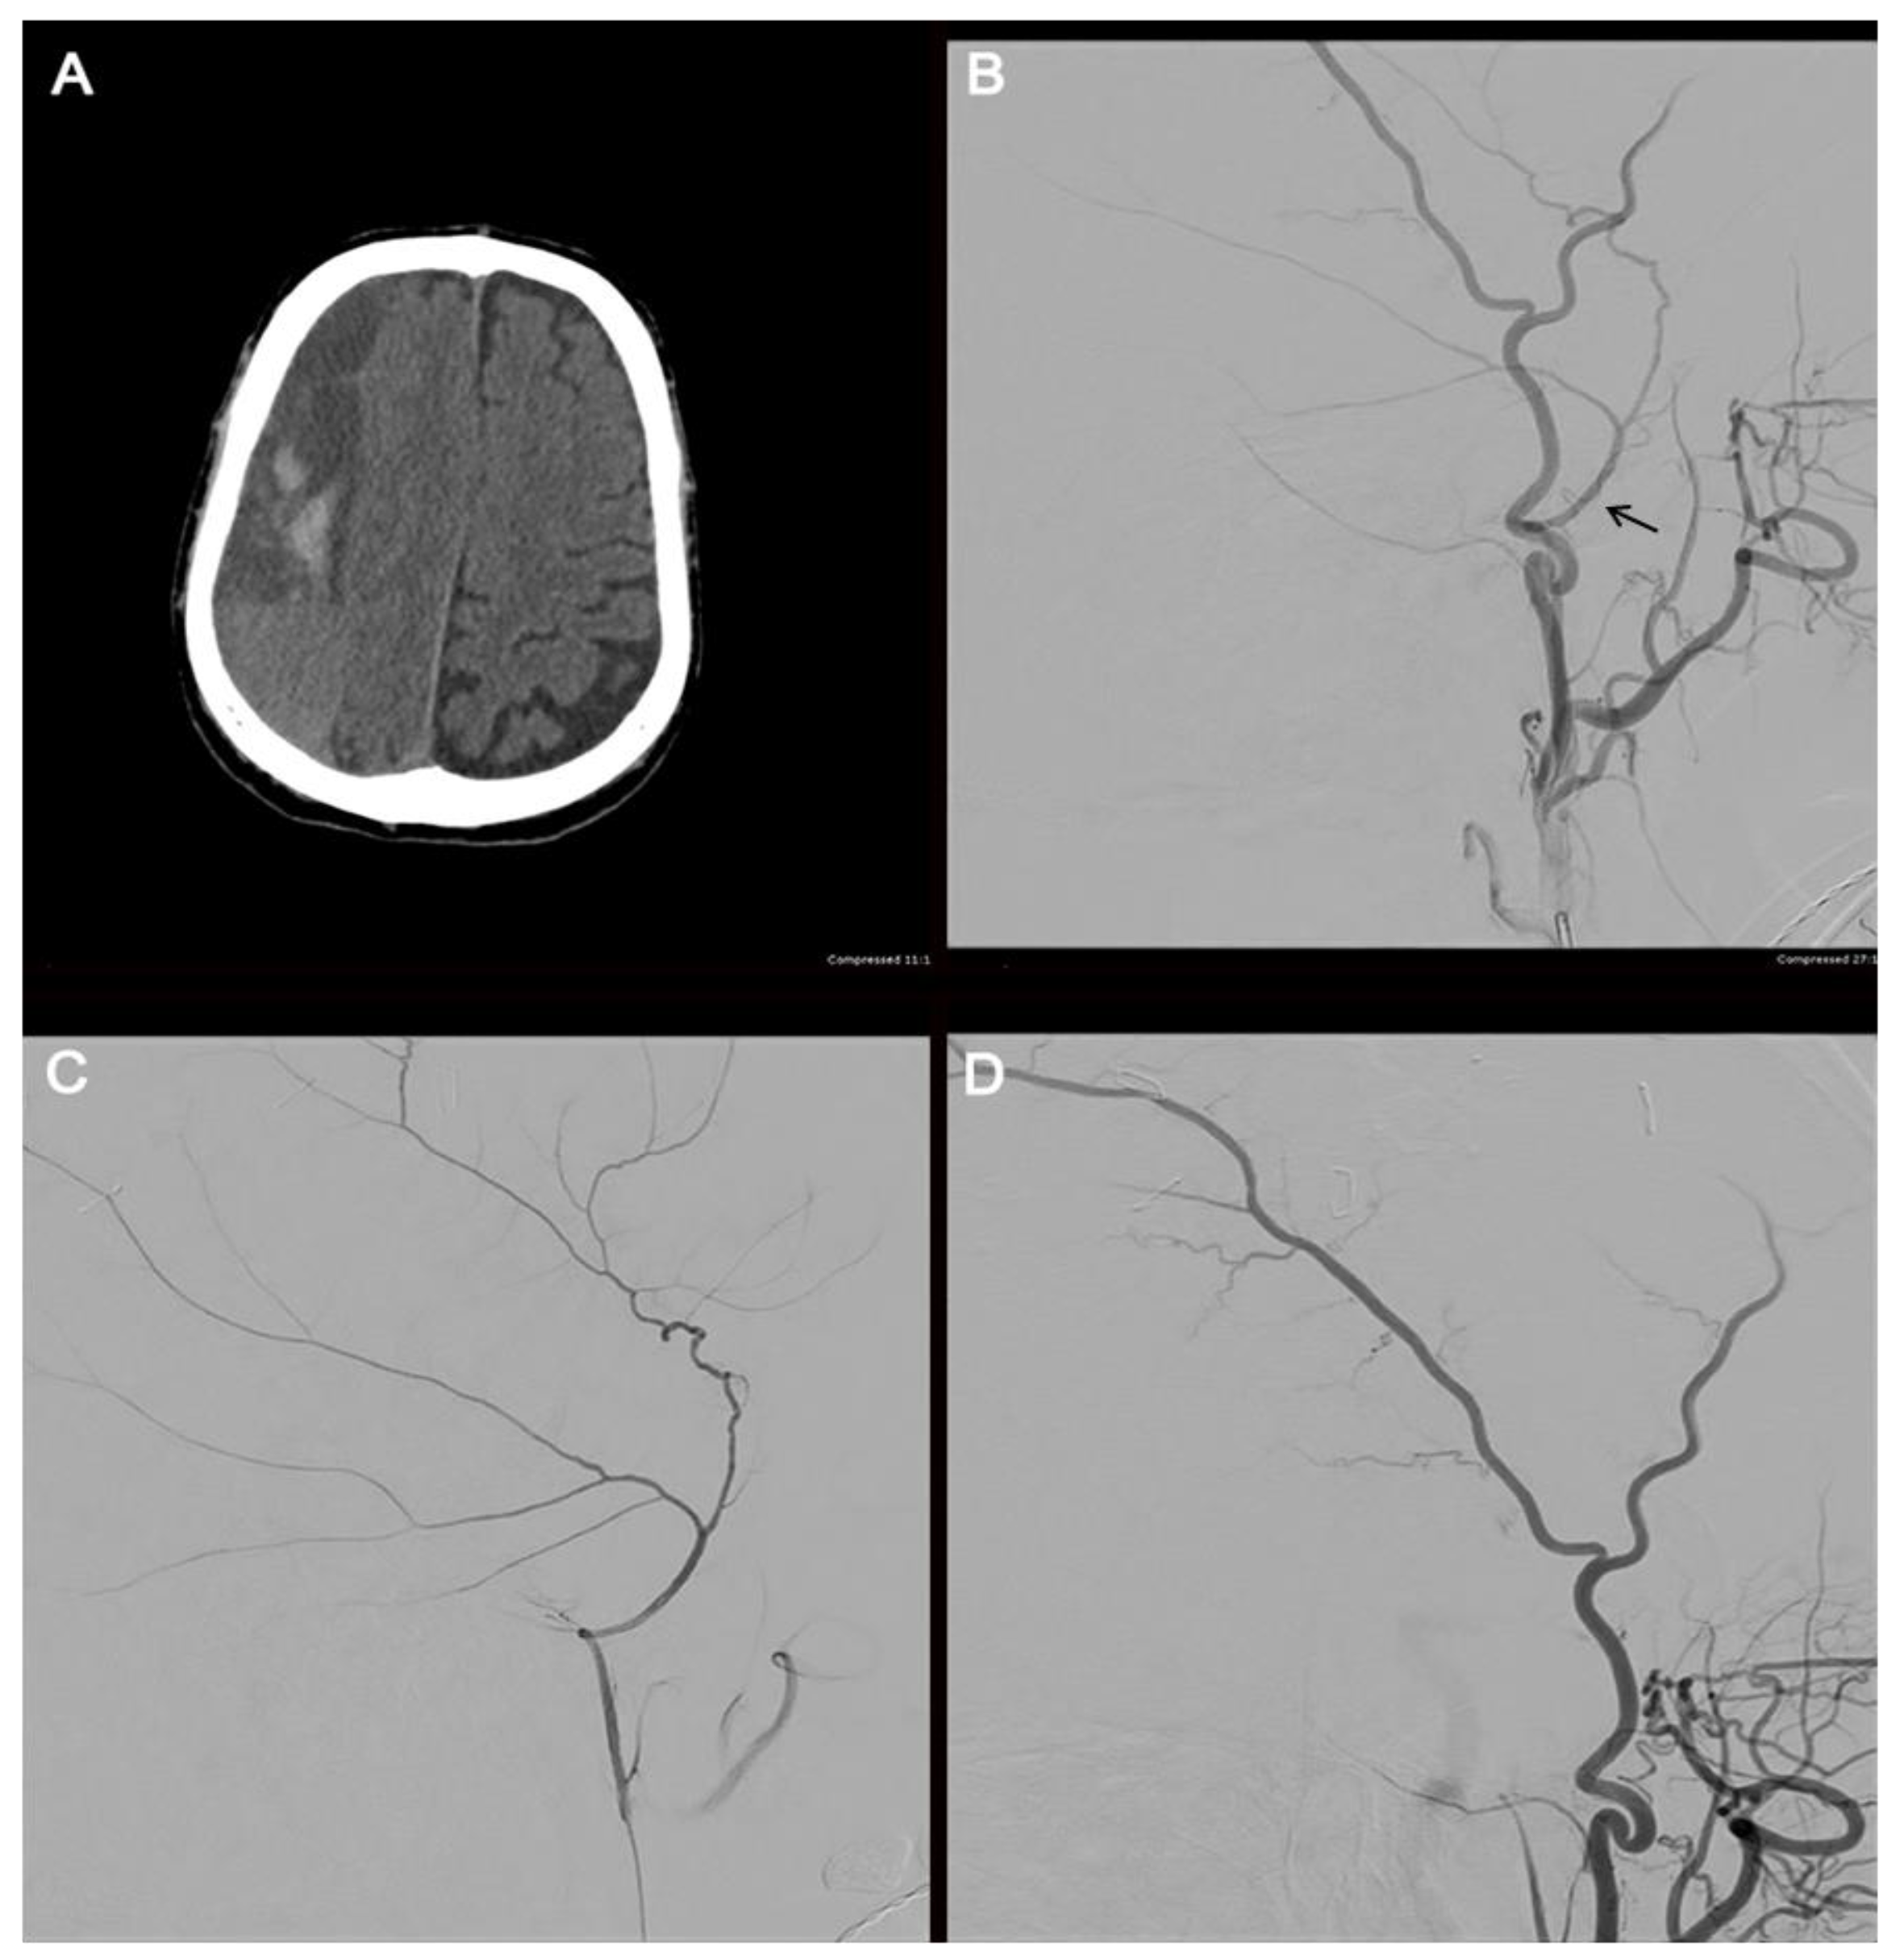

3.3. Grade IV: Occlusion

3.4. Grade V: Transection